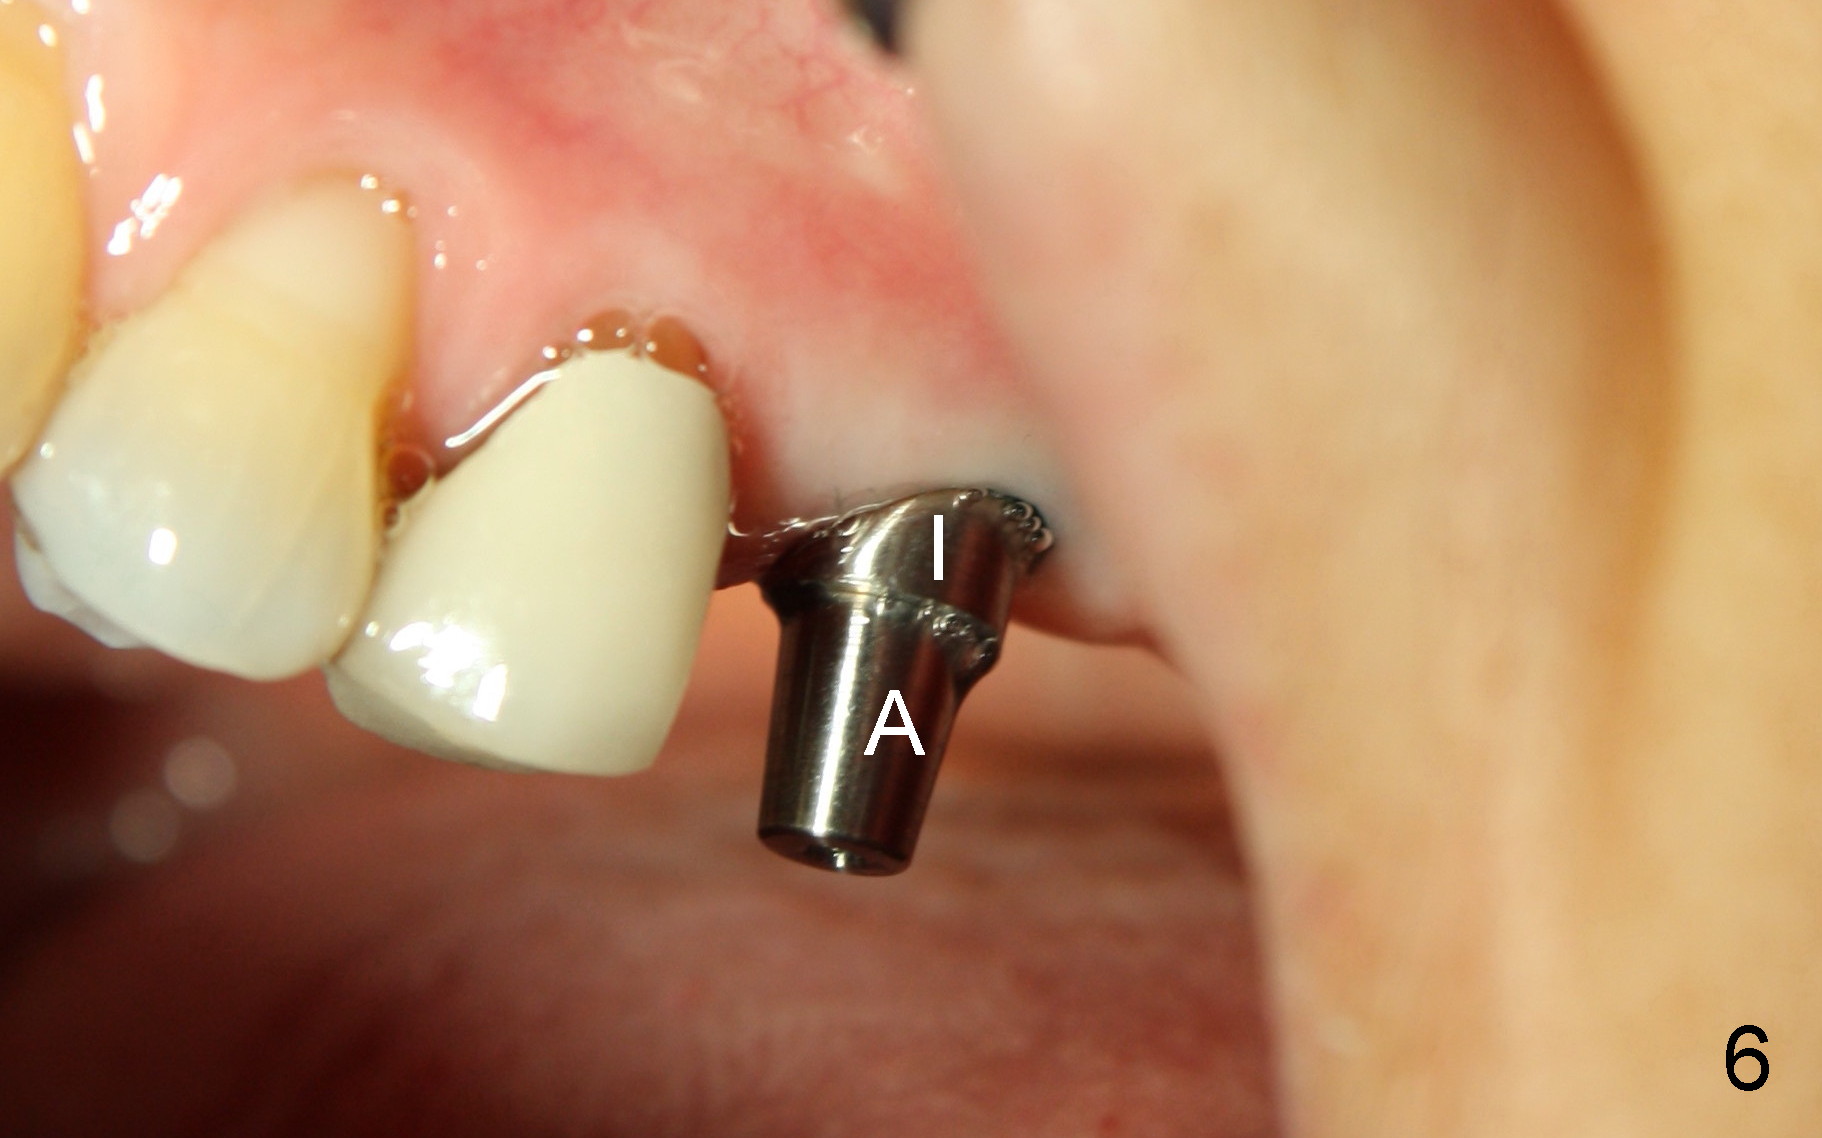

Fig.5, 6 are taken 3 and 4 months post implantation (I: implant; A: abutment).